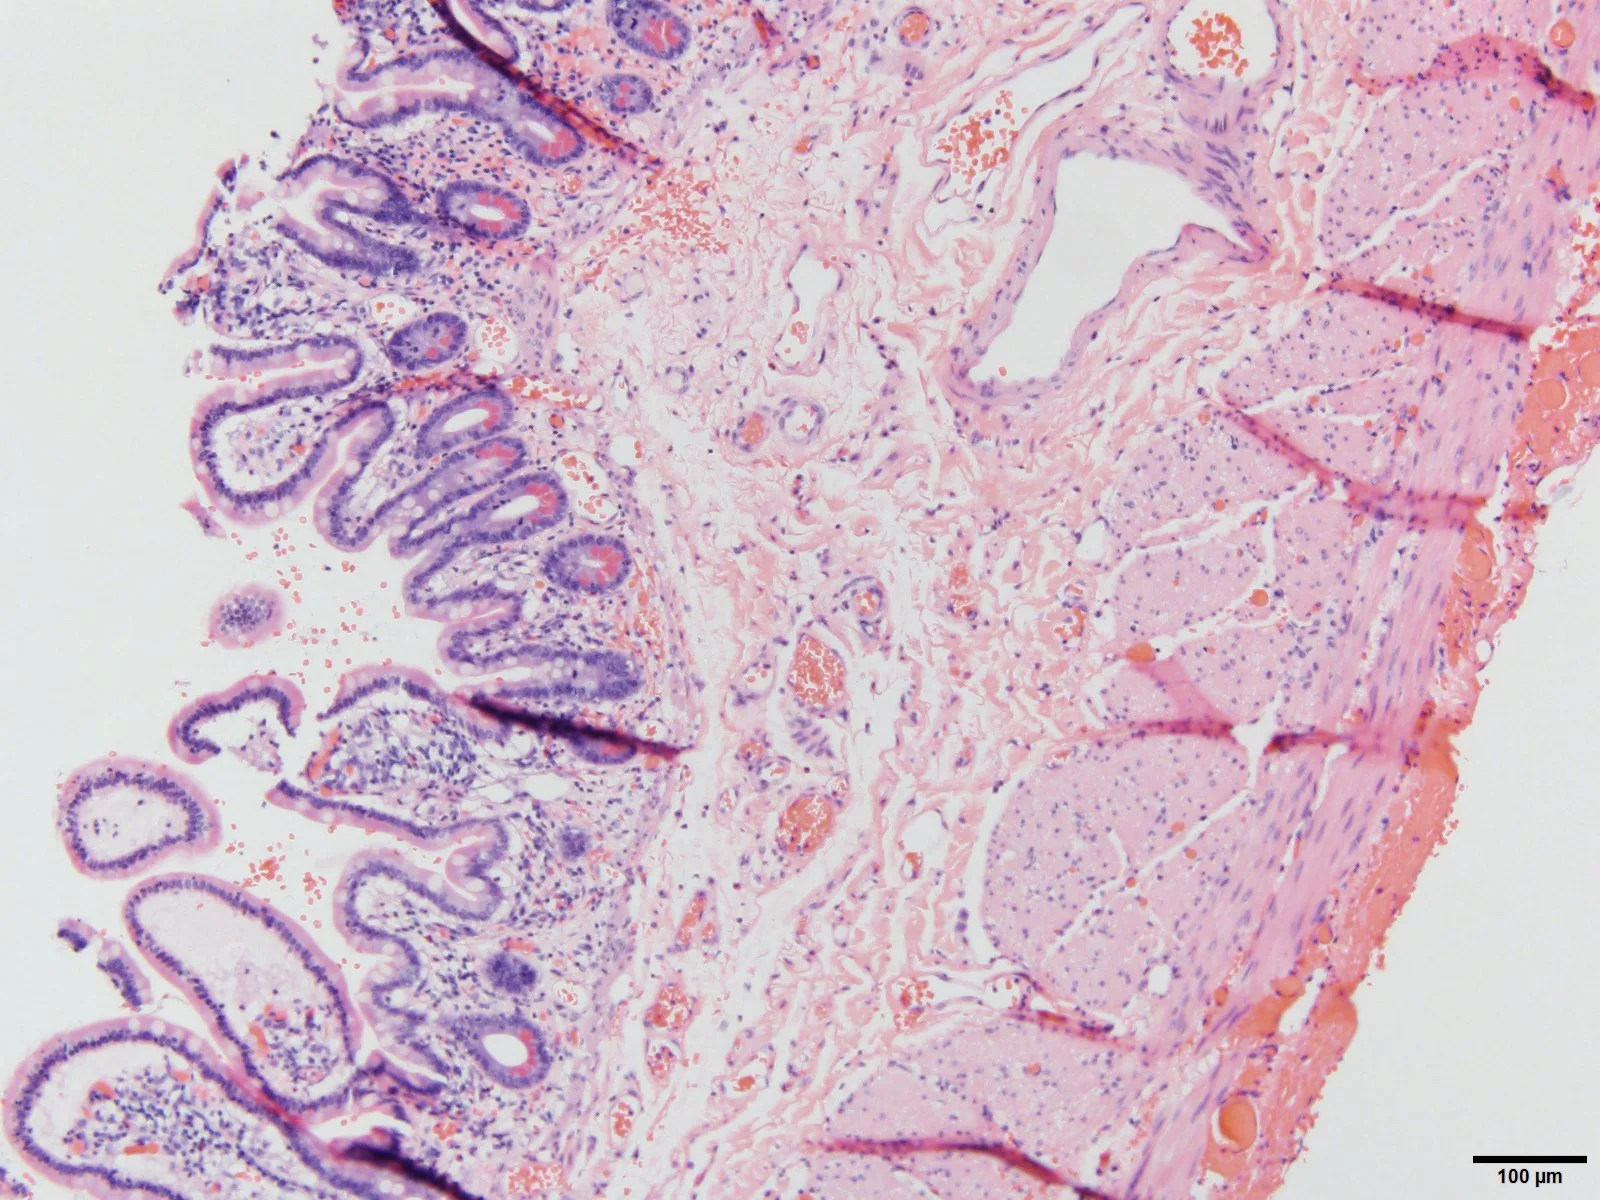

Histopath (courtesy of Dr. Cameron, HCMC): Viable bowel at the margin. Note the healthy mucosa, and a small amount of serosal hemorrhage